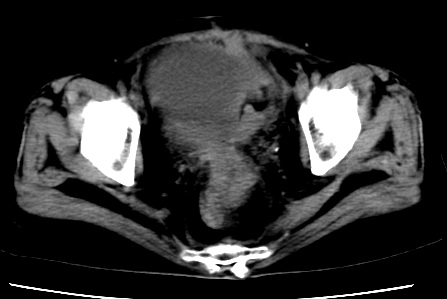

标题: CT23975:女61岁,腹部不适,明显消瘦

既往5年前卵巢癌行子宫及附件切除,右乳癌术后一年,考虑腹膜转移?

大量腹水,考虑腹膜转移。肝脏低密度灶。1囊肿,2转移。

1)结合病史,考虑腹膜及网膜转移瘤。2)肝脏多发性低密度灶,不排除转移瘤。3)大量腹水。

考虑卵巢癌行子宫术后复发,并肝、腹腔 、大网膜转移可能性大。

大量腹水。